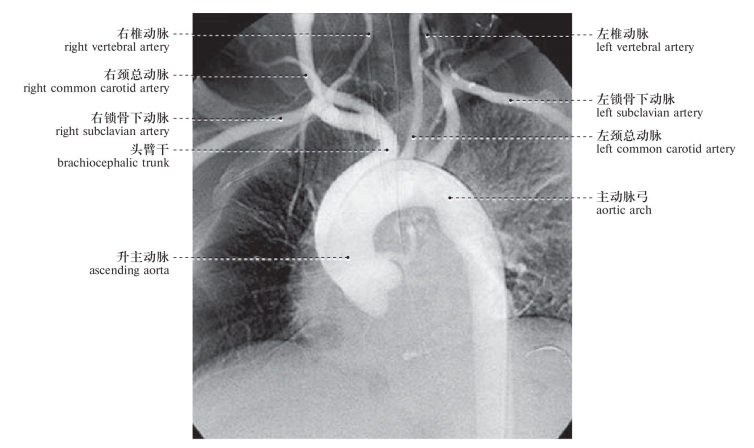

图387 主动脉弓数字减影血管造影

DSA of the aortic arch